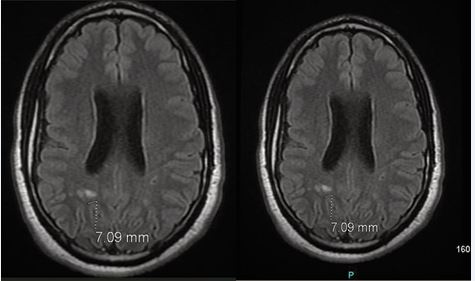

Figure A MRI brain without contrast:

Brain MRI without contrast (Figure A), demonstrated a pattern of colpocephaly with cavum septum pellucidum and mild ventriculomegaly, as well as nonspecific foci of demyelination in the posterior periventricular white matter tracts, measuring up to 7 mm and more prominent on the right hemisphere as compared to the left hemisphere. No evidence of acute infarction, hemorrhage, or mass effect was observed. An EEG was performed to further evaluate for subclinical seizures and showed no epileptiform activity.

Ventricles of the brain are somewhat prominent for a patient of this age. Cavum of the septum pallucidum. Pattern of colpocephaly. Mild ventriculomegaly is noted. Non-specific foci of demyelination are seen in the posterior periventricular white matter tracts in both the hemispheres more prominent on the right side than left. These range from 3-7 mm. No Acute infarct. No hemorrhage.